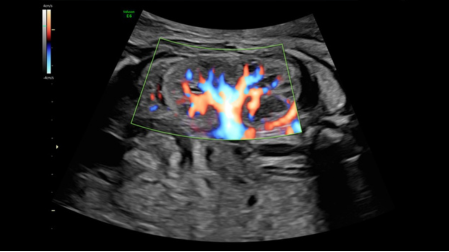

Radiantflow режим реалистичного объемного кровотока

• Поддержка режимов: В-режим, М-Режим, анатомический М-режим, импульсно-волновой допплер, ЦДК, PD, TD, стандартное 2D сканирование, объёмное сканирование 3D и 4D, объёмное сканирование 4D в реальном времени